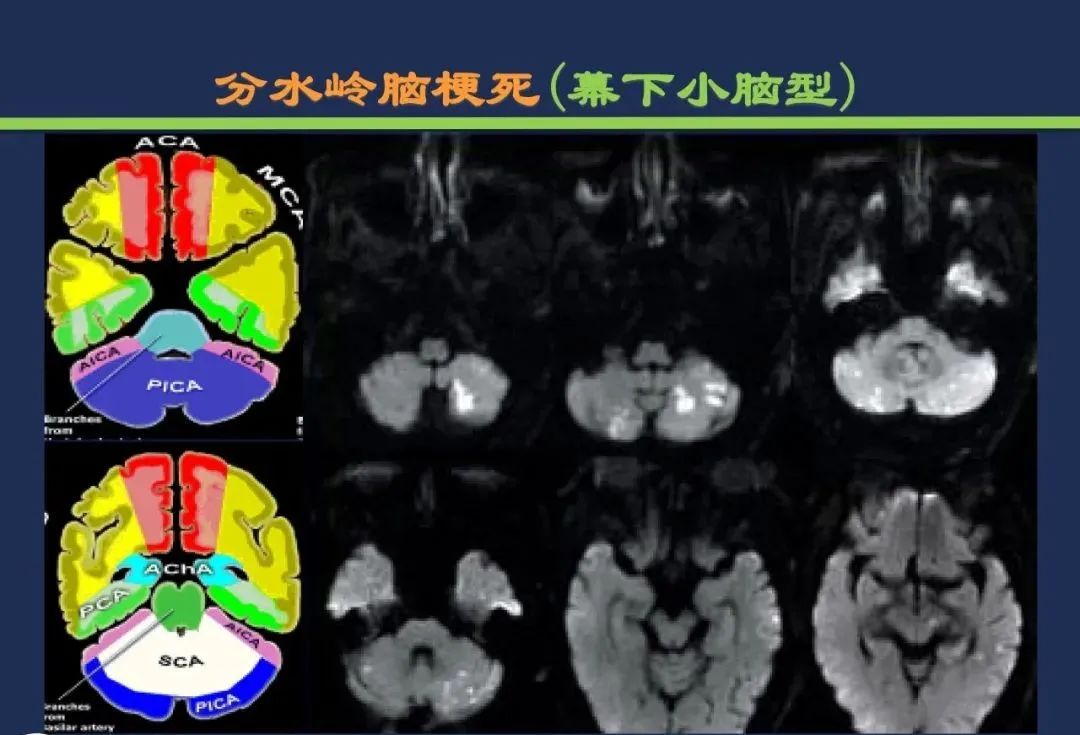

分水岭梗死皮质前型+皮质后型+后上型皮质下前型+皮质下后型+皮质下上型+皮质下外型+皮质下下型